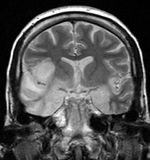

| Herpesviral encephalitis | A herpetic infection of the brain that is thought to be caused by the retrograde transmission of virus from a peripheral site on the face following HSV-1 reactivation, along the trigeminal nerve axon, to the brain. HSV is the most common cause of viral encephalitis. When infecting the brain, the virus shows a preference for the temporal lobe.[2]. | |